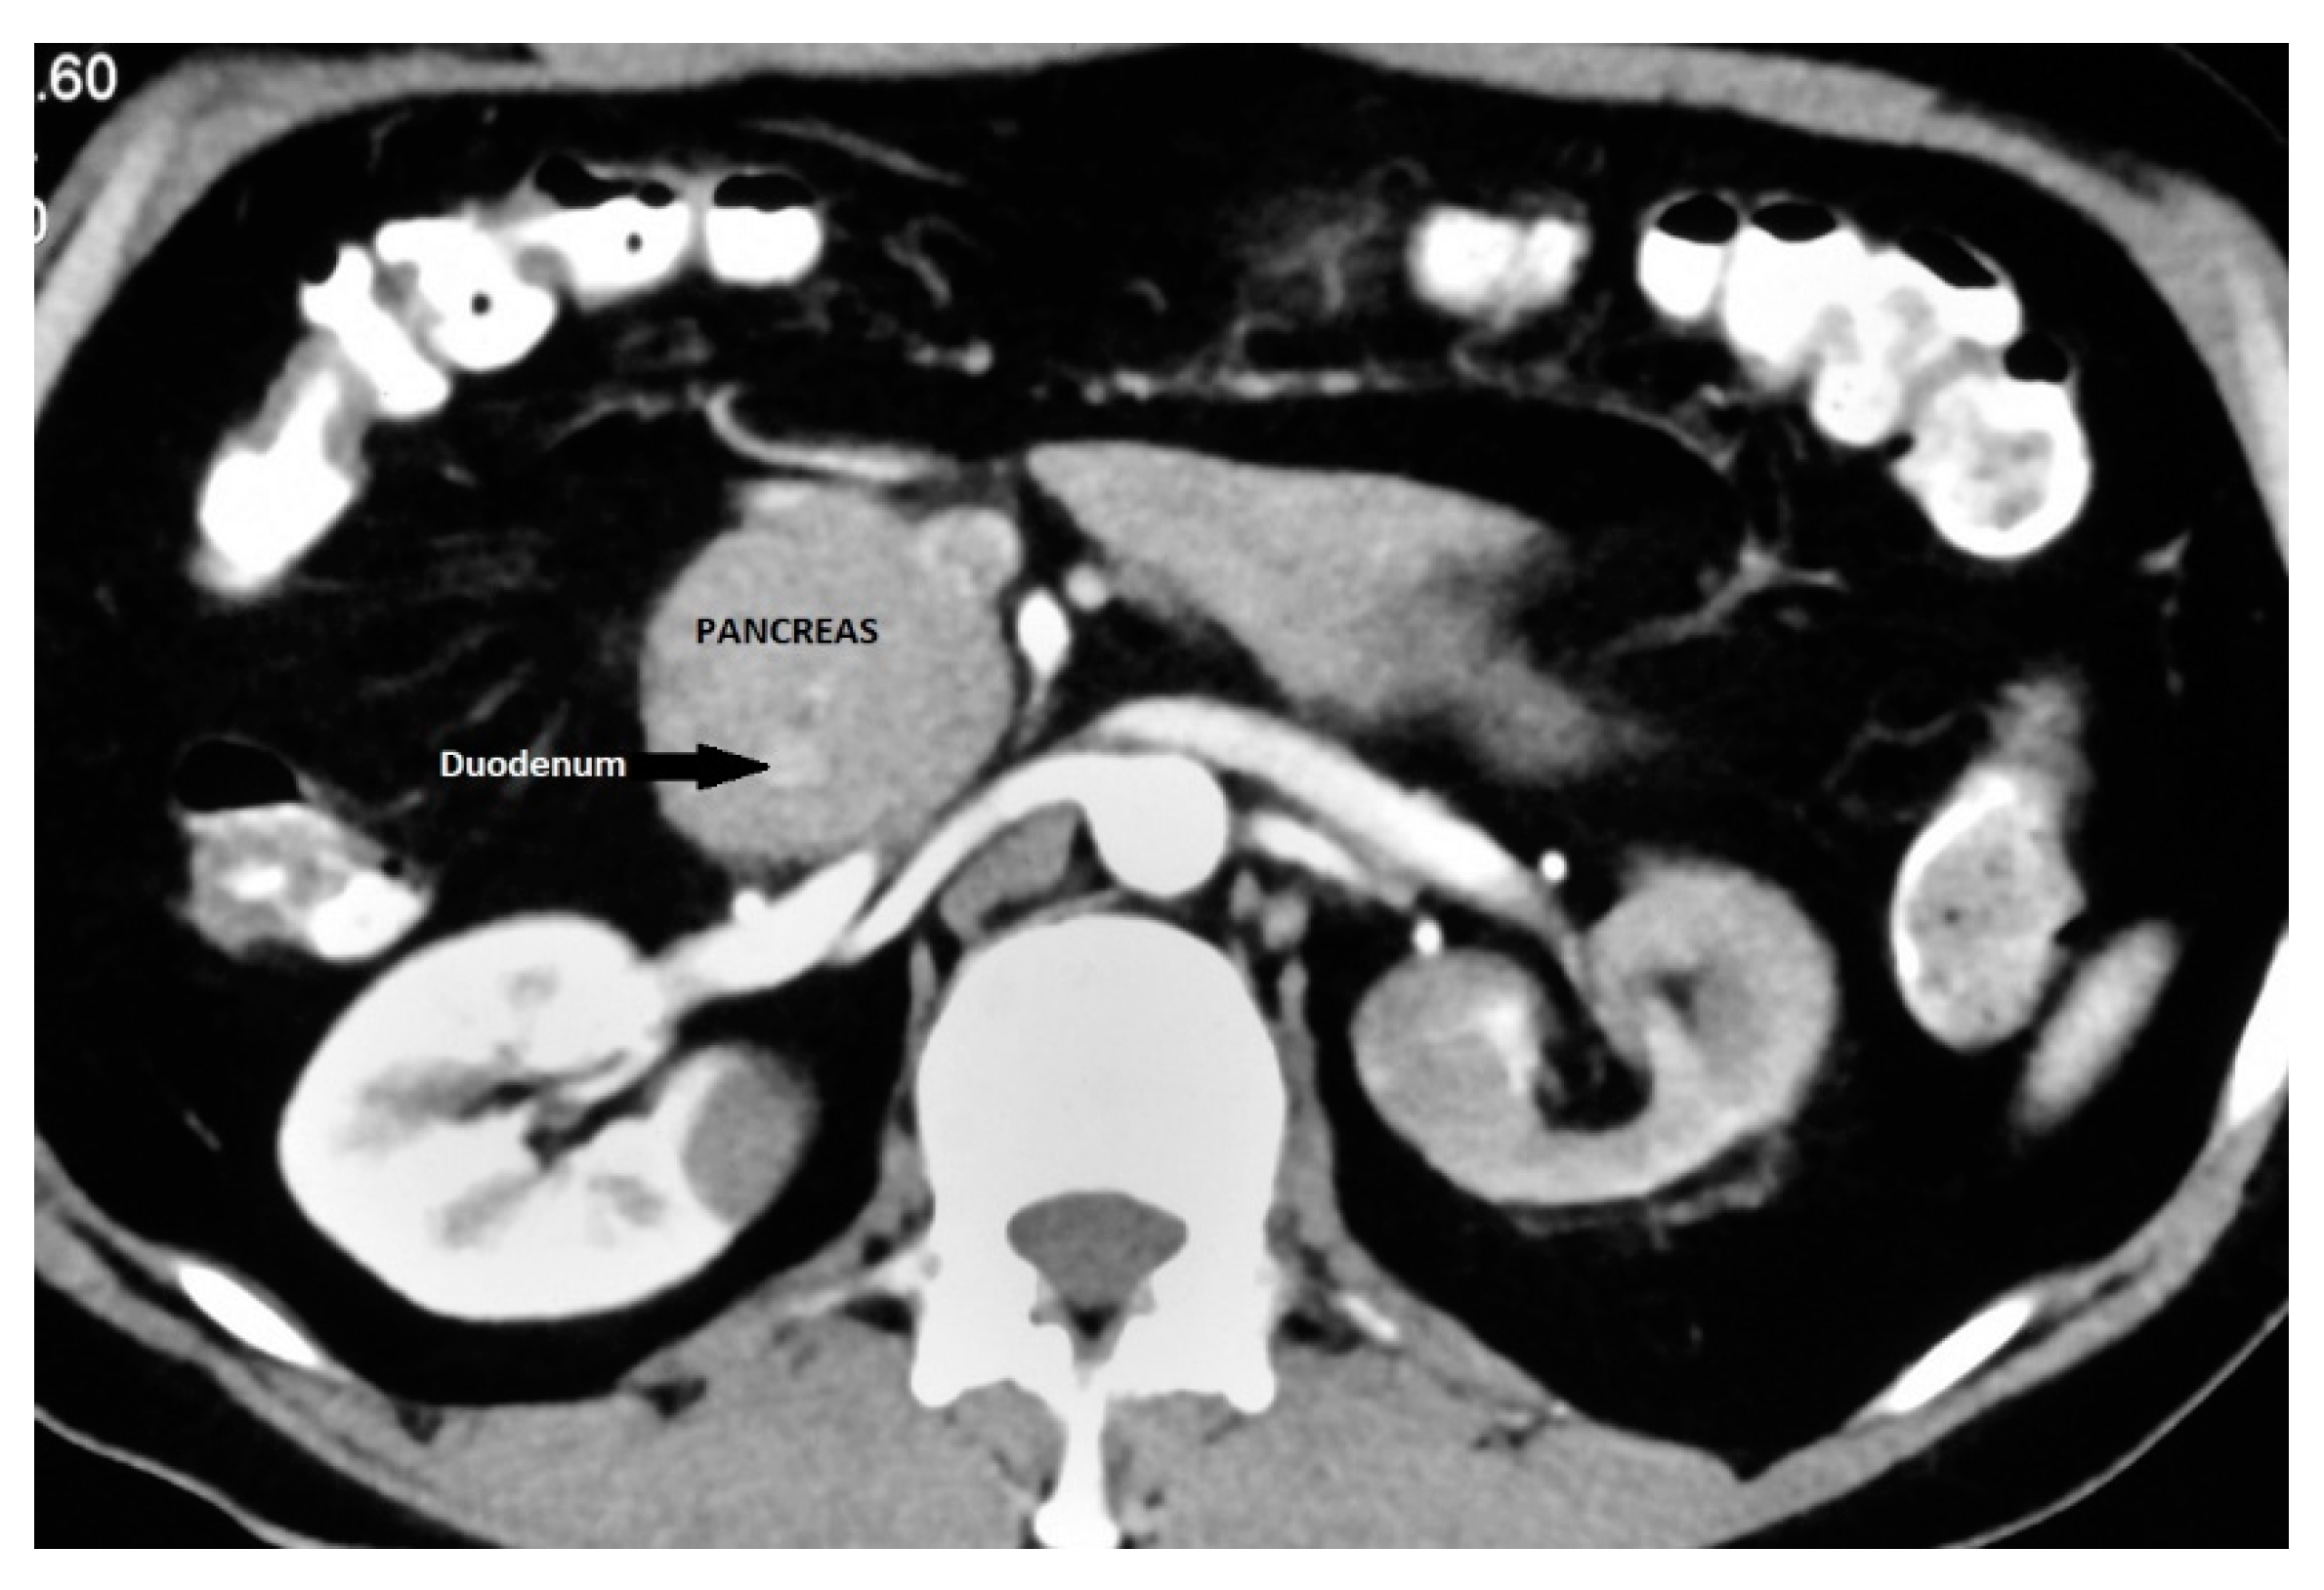

It is an important differential diagnosis for descending duodenal obstruction and contrast enhanced CT can demonstrate the enhancing pancreatic tissue around the duodenum (Figure 5).41 ERCP is considered as the gold standard for diagnosis of AP as it provides visualization of the descending duodenum and the pancreatic ductal system along with major and minor papilla.42, 43 Duodenal narrowing is usually located just proximal to the major papilla and the minor papilla is usually situated at the proximal rim of the annular ring. In majority of patients, the duct of the annular pancreas communicates with the main pancreatic duct arising from the major papilla. However, ERCP via the major papilla will not be able to diagnose AP in patients where the annular duct opens into the minor papilla or directly into the duodenum.44 Moreover, ERCP is technically difficult in patients with significant duodenal obstruction. The annular duct can also be detected on MRCP where it commonly connects with main pancreatic duct near the major papilla but also may drain into the dorsal duct near the minor papilla or directly drain into the duodenum.45 MRCP, apart from being non-invasive and operator independent, can also visualise pancreatic parenchyma around the duodenum.

Figure 5. Annular Pancreas: CECT showing pancreatic tissue encircling descending duodenum.